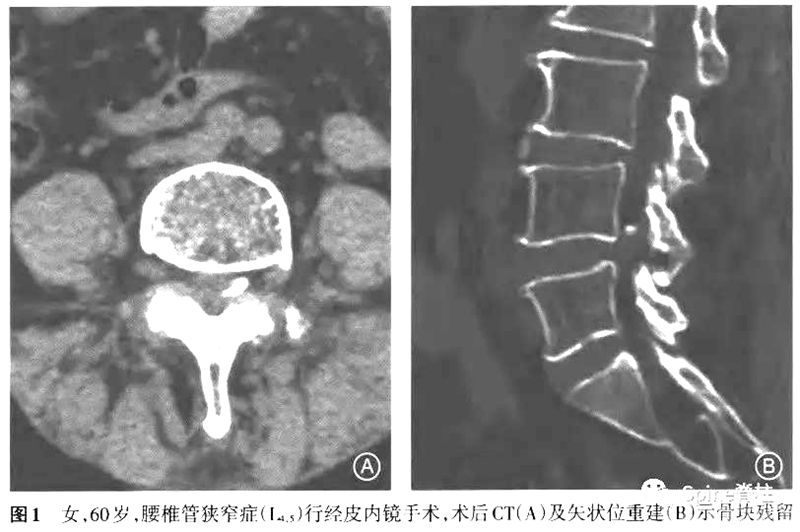

PTED术后常见的并发症,如术中神经根刺激或损伤、术后血肿、术中硬膜囊撕裂、术后椎间盘髓核残留或复发等,大家都比较熟知。然而,一种少见的可能并发症(即症状性关节突关节骨块残留,symptomatic facet of residual bone mass)开始受到关注,有学者认为PTED术中于关节突关节进行椎间孔成形操作属于盲视下操作,即使应用术中X线透视,仍无法精确控制骨块移除的量,因此出现关节突关节骨块残留有一定的可能性。

2.残留骨块移位可以导致椎间孔和椎管内的占位,进而形成椎管狭窄的相应症状。

所有7例患者在经皮内镜手术中均进行了椎间孔成形操作。5例为术后立即出现症状,1例为术后1周出现症状,1例为术后1个月出现症状。经保守治疗后,1例患者症状好转拒绝手术,2例出现对侧的刺激症状,余4例均为原症状加重。其中因残留骨块刺破硬膜囊出现脑脊液漏者2例,残留骨块损伤神经引起下肢肌力下降1例。术后CT提示5例骨块在椎问孔成形同侧,2例在对侧。